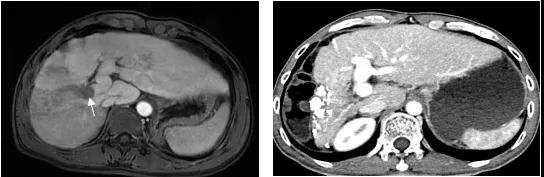

图1、病例54岁,肝右叶5.5×5.4cm肝癌(左图),行TACE+消融肿瘤完全坏死并缩小(右图),现患者已生存14年。